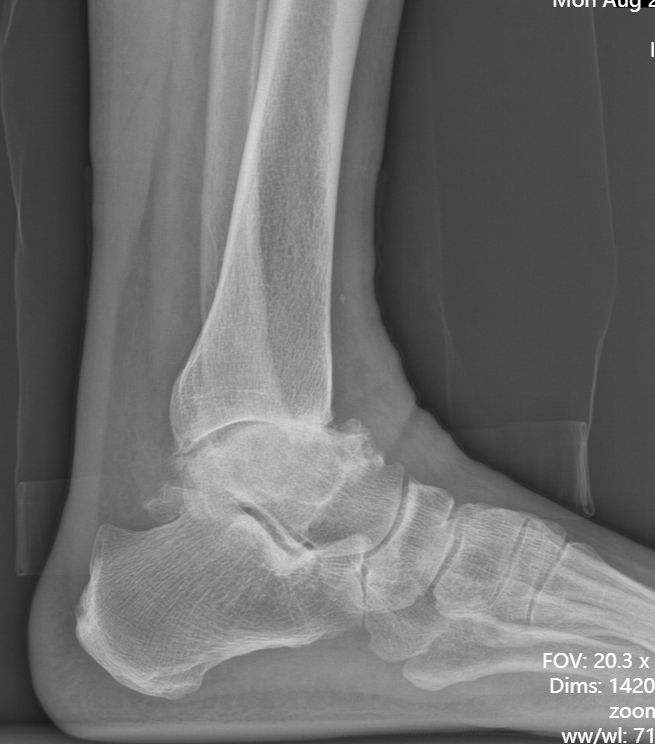

第一台手术的患者是位75岁的叔叔,被“脚脖子”痛缠了4年,疼得越来越厉害,病情已经到了严重阶段。

术前踝关节侧位X线

武勇主任团队给他做了3D打印导板辅助下人工全踝关节置换术。

这种手术适合踝关节病严重的患者,通过替换病变的关节结构,能帮着缓解疼痛、恢复关节活动,让老人日常走路更自在些。